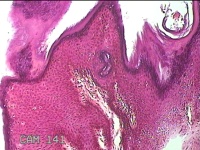

会阴部肿物

性别

男

年龄

47岁

临床诊断

1.皮肤肿物 2.尖锐湿疣?

一般病史

发现会阴部皮肤肿物2个月余。

标本名称

大体所见

灰白粉红色皮肤肿物0.8x0.5x0.3cm一个,表面光滑。

图1

首先考虑湿疣。

良性病变。